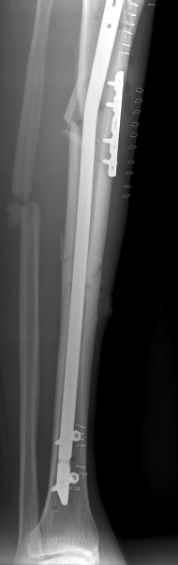

Молодой женщине по поводу бамперного перелома через 2 недели после травмы выполнен остеосинтез большеберцовой кости гвоздем ChM в одной из больниц Москвы. Снимок приложен. Сейчас речь пошла об удалении гвоздя и остеосинтезе пластиной. Действительно ли это оптимальный план? Какие есть еще варианты?

A female 24 years old, a sister of a friend of mine (not physician) living in Moscow, 3 weeks ago admitted to the hospital in Moscow after a car accident (was a pedestrian) with a tibial shaft fracture. 3 days ago closed locked nailing was performed, see attached films. Now he is in panic because they are going to remove the nail and perform plating.

1.Насколько видно, снимки сделаны в разное время - фасный позже, когда отломки уже "стелескопировались" на гвозде.

2.Трудно сказать, насколько хорошо отломки стояли на момент окончания операции, но из-за введения проксимального статического винта мимо отверстия угловая деформация и укорочение усугубились до непримлемых.

The tibia shaft fracture (proximal 1/3 of the shaft) is apex medial 20 degrees, slightly short and a few degrees apex anterior after nailing. The nail extends quite proximal to the entry site. I wasn't able to see the distal end of the nail on my screen and am not certain if there was distal locking.